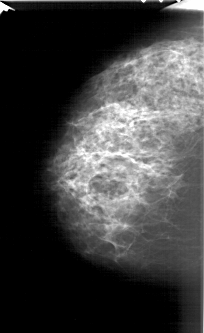

A_1374_1.LEFT_CC

LEFT_CC LINES 5656 PIXELS_PER_LINE 3466 BITS_PER_PIXEL 12 RESOLUTION 43.5 NON_OVERLAY